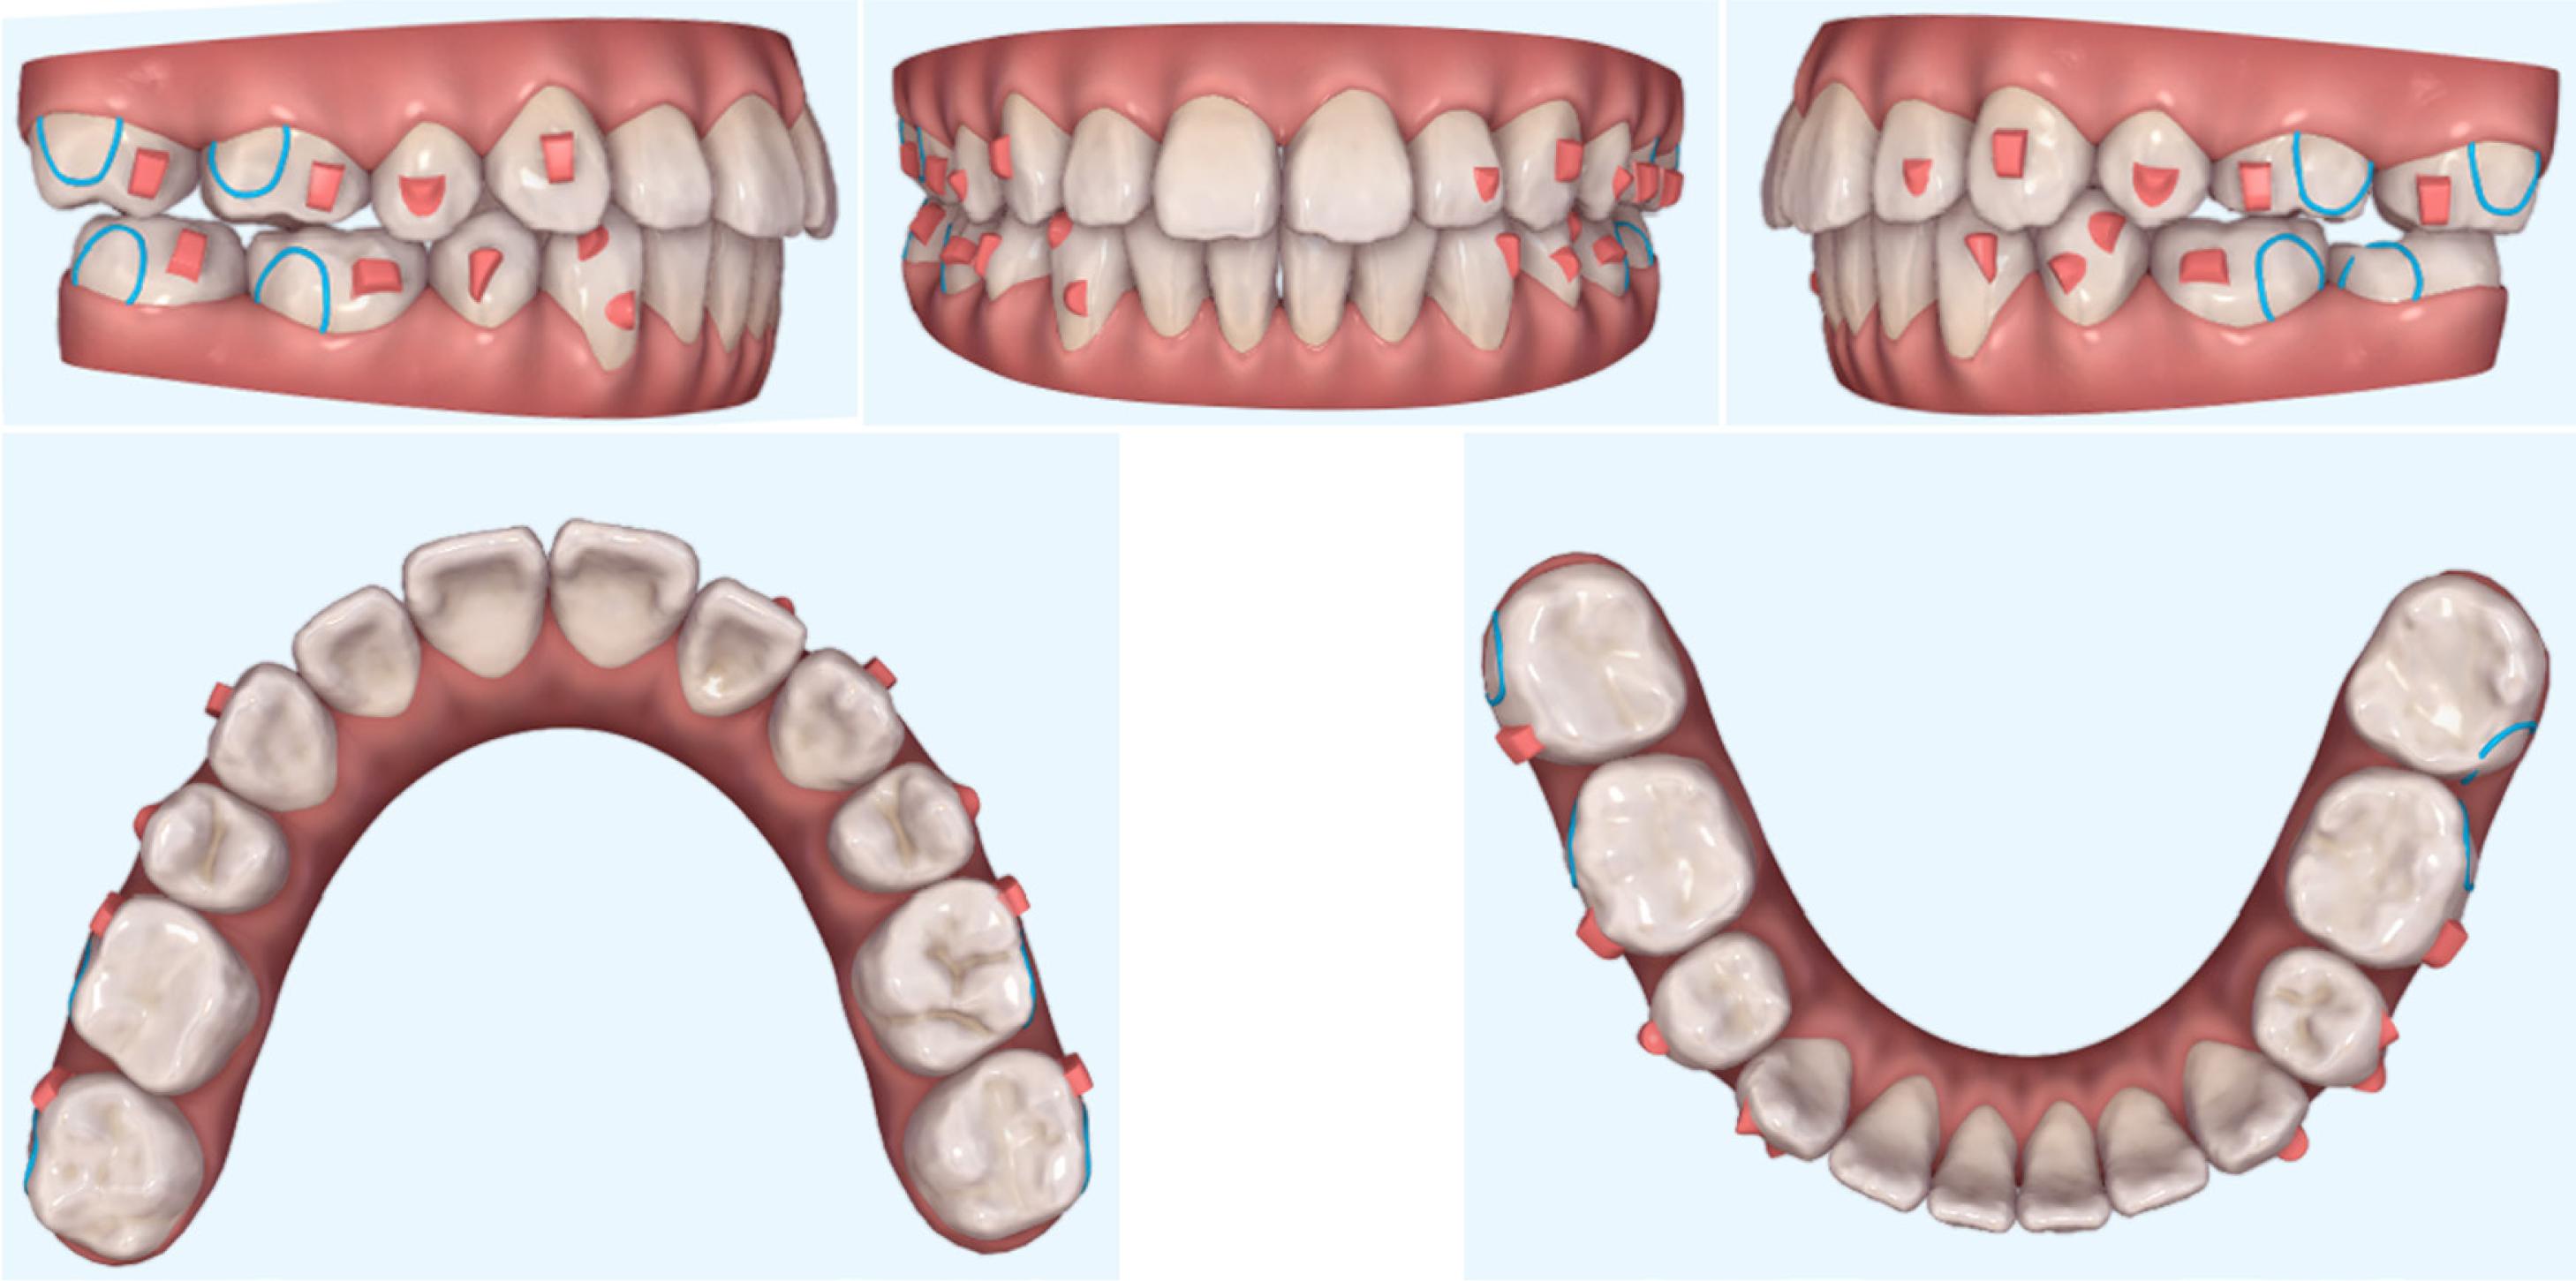

Figure 4.